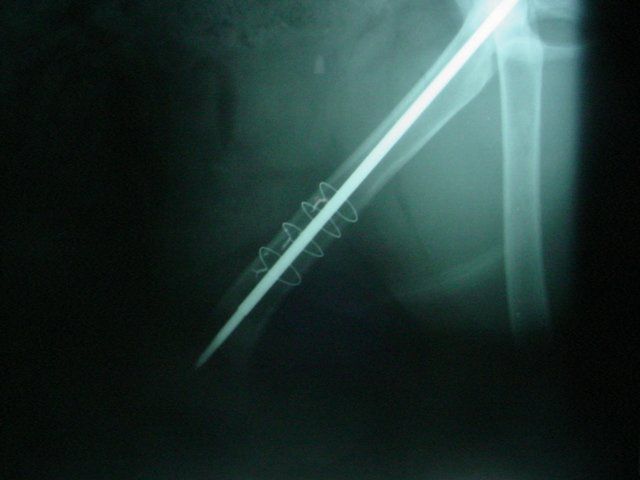

Dogs and cats commonly experience fractures secondary to trauma. The most common cause of the trauma is being hit by a car. Other trauma such as falls from furniture, jumping on unstable surfaces, leaping from a person's arms, etc. can also result in fractures. Below are some x-rays of some of the fractures we have seen at All Pets and their surgical correction using pins, plates, screws, and/or wires.